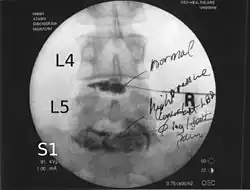

Lumbar provocative discography showing a degenerated disc, L5-S1 with normal disc L4-L5 | |

Spinal MRI is the imaging of choice to investigate the spine and intervertebral discs.[1] Meanwhile, lumbar discography is used to demonstrate degeneration and herniation of lumbar intervertebral discs by injecting a dye into the nucleus pulposus of the discs. The procedure is also used to reproduce pain back pain for those who have such symptoms. Lumbar discography is also used to access the response of a subject to anaesthetic injection. Other uses include suspected discogenic pain without radicular sign (pain travelling to lower limbs along a dermatome) and confirmation of normal intervertebral discs above and below a site before spinal fusion.[1] However, evidence supporting the usefulness of lumbar discography in recognizing intervertebral disc problems is limited.[1] There is no role for cervical or thoracic discography in diagnosing disc pathologies at the cervical or thoracic regions.[1][2]

Non-ionic contrast media such as iopamidol and iohexol are used.[1] Needles are inserted through the back into the disc near the suspect area, guided by fluoroscopic imaging. Fluid is then injected to pressurize the disc, and any pain responses are recorded.

A contrast agent is introduced, and after the procedure, a CT scan identifies leakage from the discs to identify any spinal disc herniation.